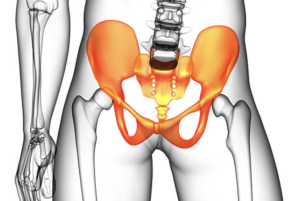

下腹部が痛い原因① 仙腸関節が硬くなっていないか?

なぜ?そんなふうに思うかというと、男の子の仙腸関節がぎっくり腰の大人よりも硬いからです。

でも、整体歴37年の私から言わせれば、動かなくていい関節なんてありません。特に、仙腸関節は、ぎっくり腰の時は必ずといいほど硬くなっていますし、仙腸関節を緩めるとぎっくり腰はスーッと改善します。

私の経験的には、仙腸関節が硬い側の下腹が痛くなることはよくあることです。

こんなふうに、内科や泌尿器科、婦人科など医療機関で異常なしなのに下腹が痛いときは、私の経験則では、[仙腸関節+αが硬い]です。

仙腸関節 + α の α が何かを探してみよう

ですが、大人が下腹が痛いと訴える場合は、さらに診ておくべき筋肉があります。それが、仙腸関節+のαの部分です。

αが何かというと、それは腸骨筋

下腹部が痛い原因② 腸骨筋の緊張はないか?

腸骨筋は腸骨の裏面で、腸骨稜の1センチくらい奥から大腿骨の小転子ついている筋肉です。この筋肉が硬いかどうかは、AIIS(上前腸骨棘)の内側を通過する腸骨筋の筋膜を触ってみて下さい。

ちょうど上記イラストの丸印の部分です。腸骨(ASIS)の内側触って異様に固く感じたり、「そこ!痛いです!」などと言われたら、腸骨筋が緊張している証拠です。そのような場合は、仙腸関節の動きを正常にした後に、仰臥位で、腸骨筋の起始の繊維を緩めてみて下さい。

正常なら、腸骨筋がASIS(上前腸骨棘)の内側を通過する部分は痛くも痒くもありません。でも、下腹が痛いという時はこの部分が固く、患者さんも痛みを感じます。

と、訴えるお客様がおられたら仙腸関節の硬さが原因、さらに腸骨筋の緊張が加わることが原因のことが多いです。